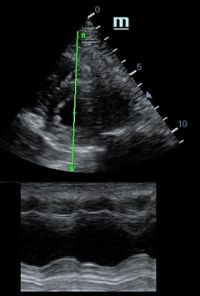

Оценка сокращения сегментов левого желудочка на глаз постепенно уходит в прошлое. Если в приборе нет функции радиального или лонгитудинального стрейна, на помощь опять может прийти Free Xros. Утолщение более 5 мм в систолу – нормальное сокращение, 2-5 мм гипокинез, истончение в систолу – дискинез.